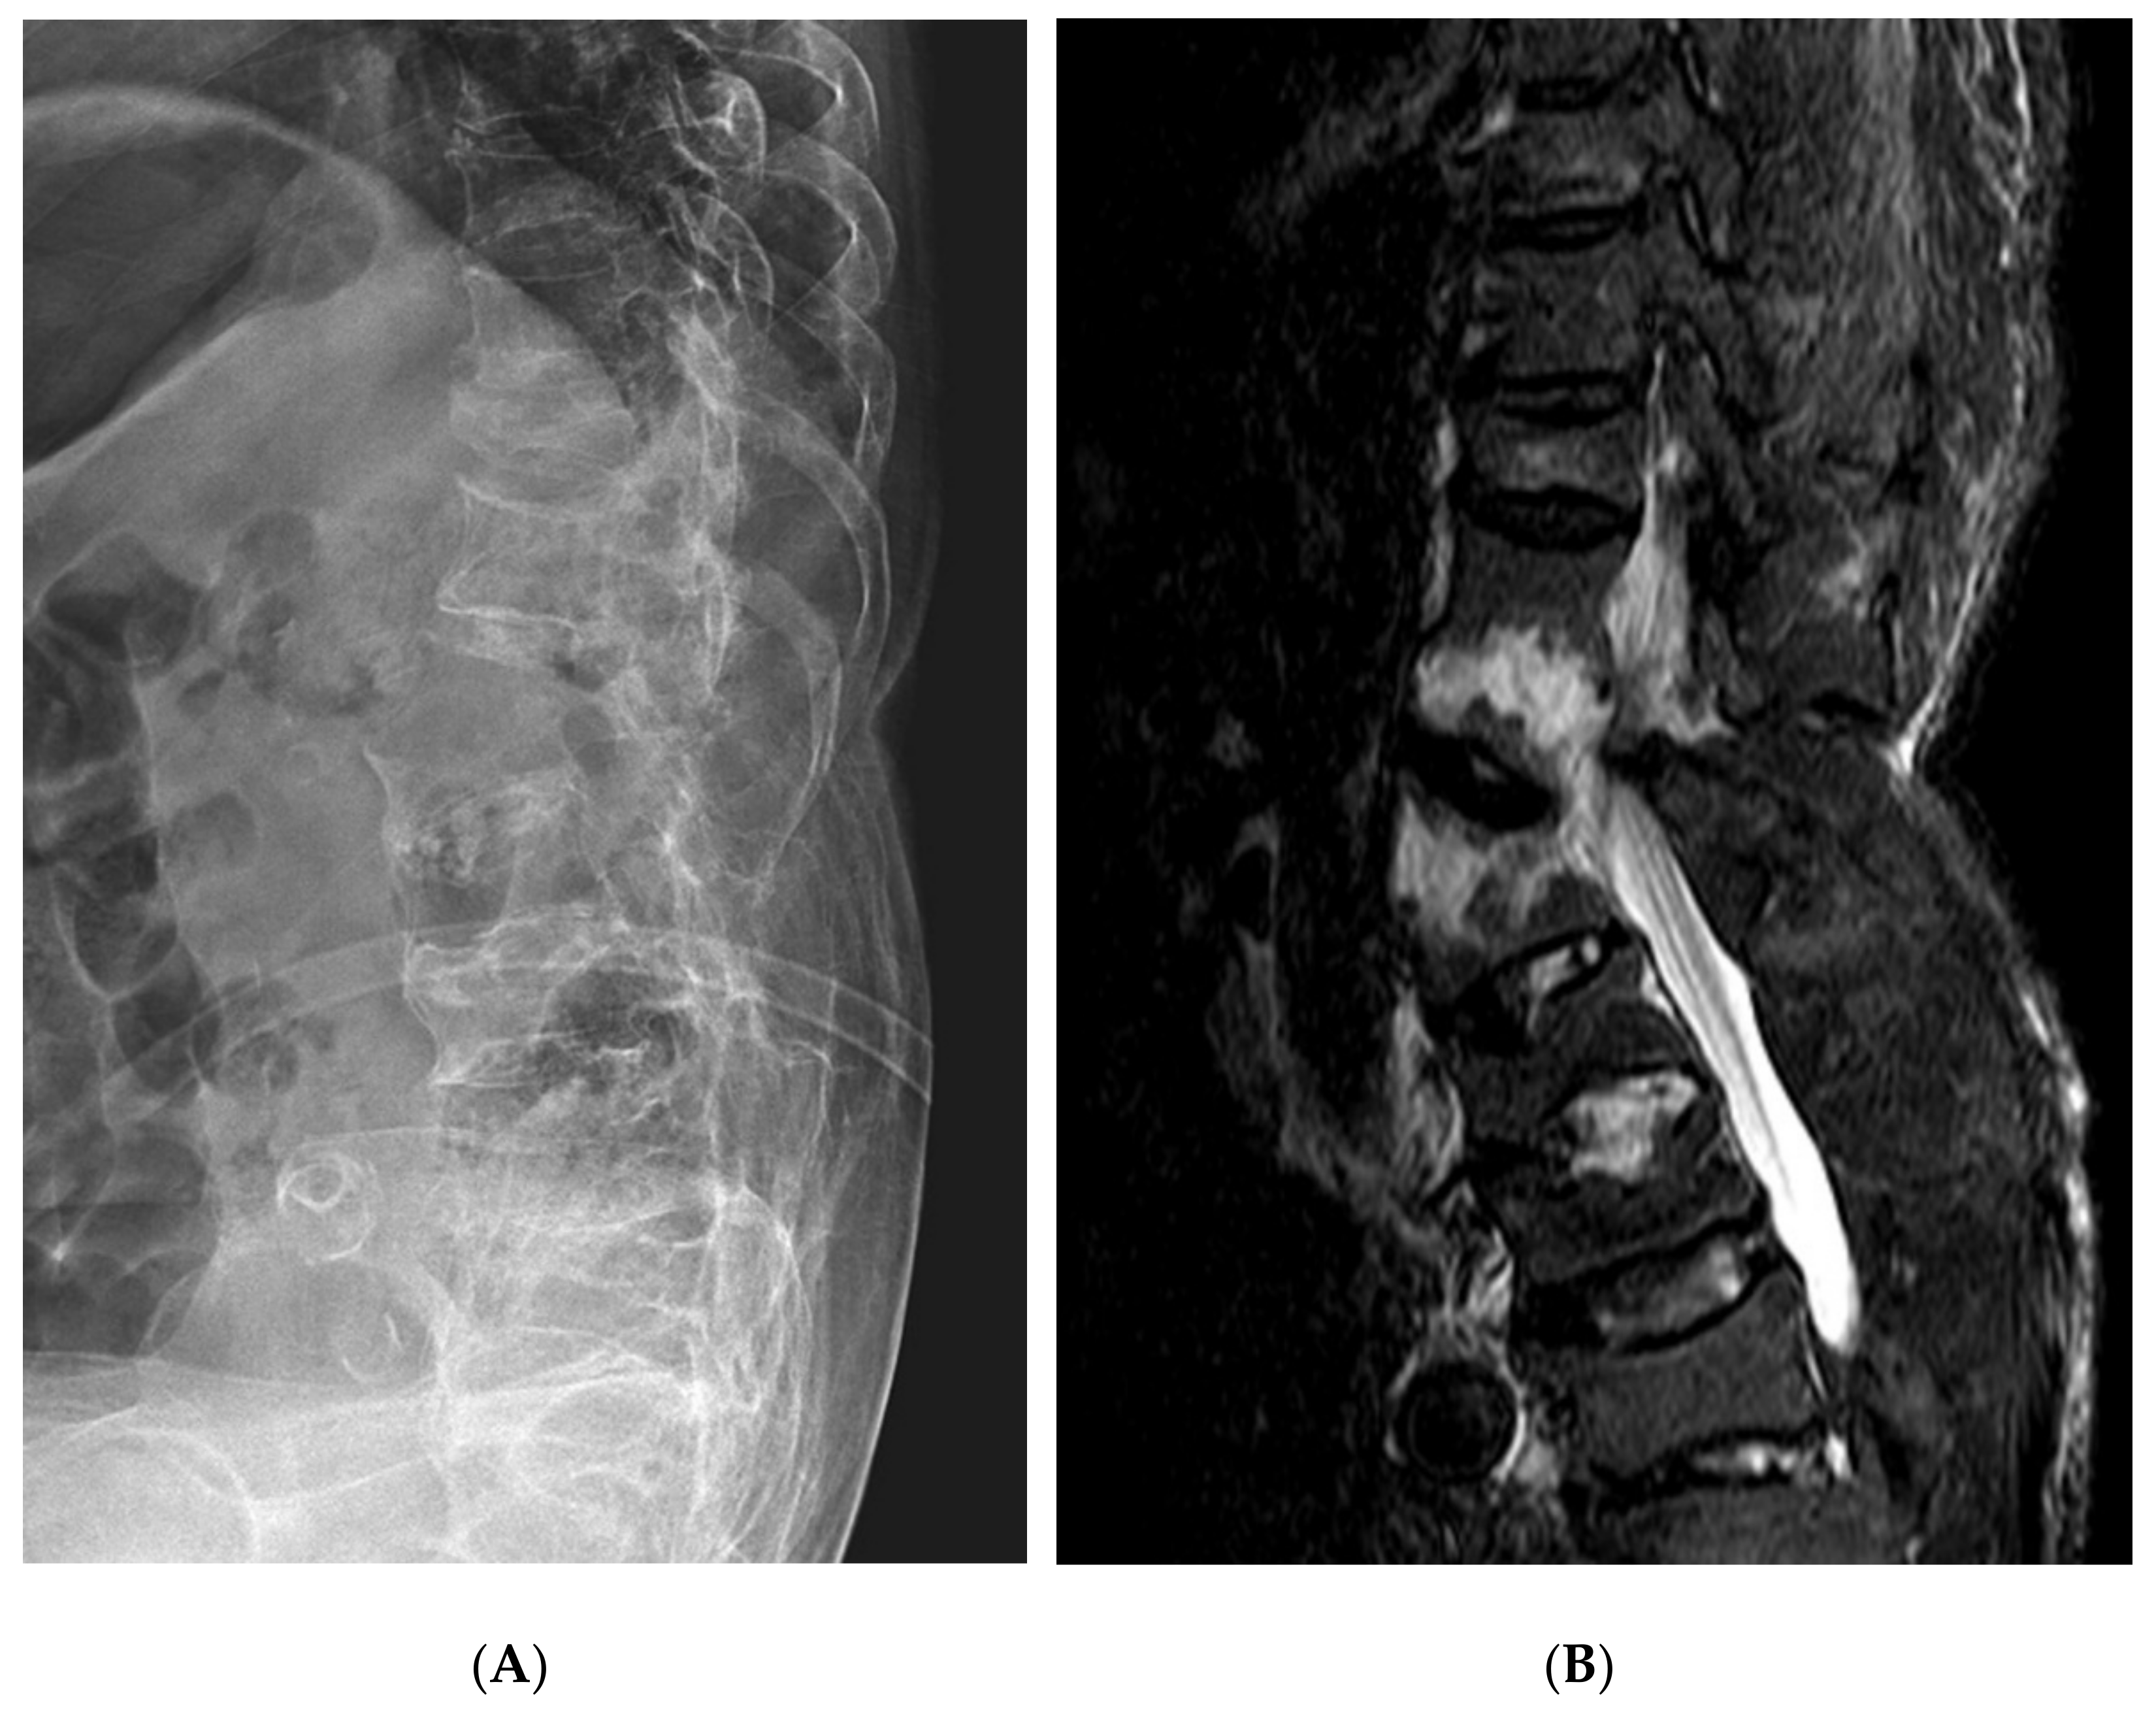

2. Case Presentation